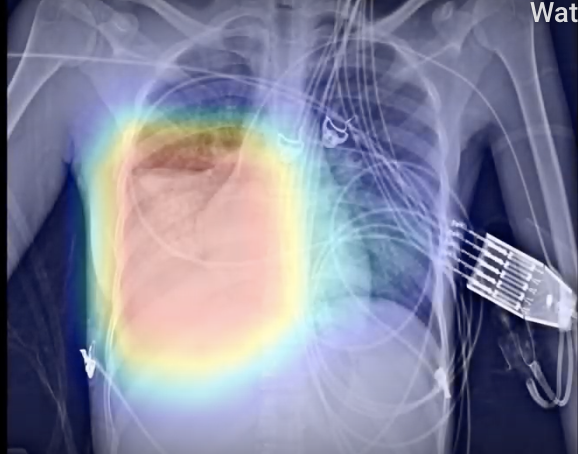

Covid19 Lunit Inc

Ai Algorithm Identifies Chest X Rays From Covid 19 Patients As Abnormal Imaging Technology News

Ferramenta De Ia Identifica Casos De Covid 19 Por Radiografias

Inteligencia Artificial Classifica Radiografias De Torax Com Precisao No Nivel Humano Data Science Academy